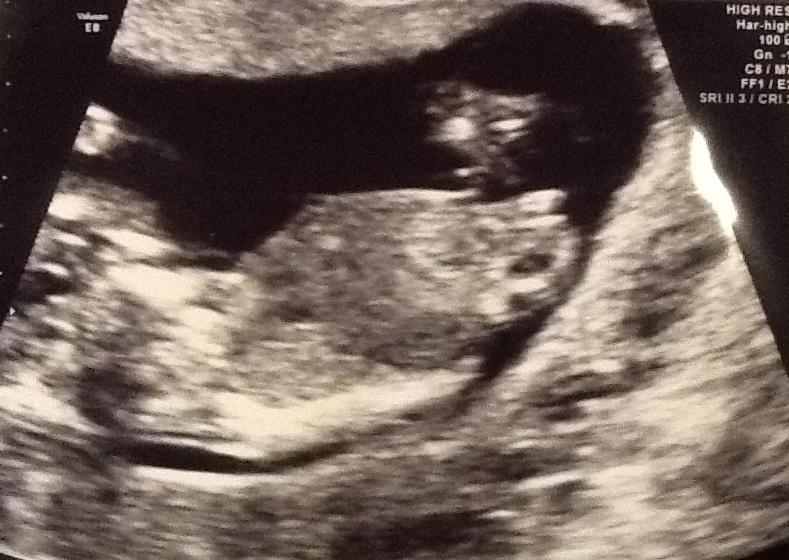

This is my 13 week ultrasound. Would love some guesses. Never found out with my last two, this time I can't wait to know. Thanks in advanceAttachment 13121

Thinking girl but its not all that clear

I thought girl too when I first saw it but I am still pretty new to nub guessing. It looks pretty paralall to the spine